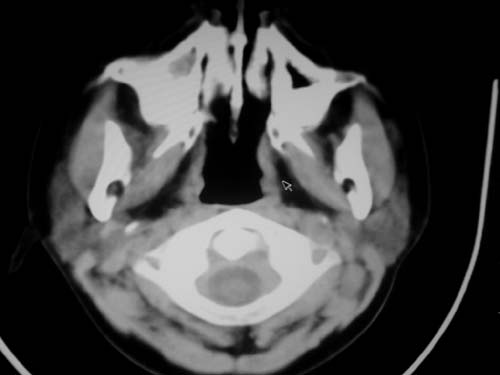

标题: CT19740:女,12岁,鼻塞,流黄鼻涕。 [打印本页]

标题: CT19740:女,12岁,鼻塞,流黄鼻涕。

双侧上颌窦炎,增殖腺肥大。

1)双侧上颌窦炎。2)鼻咽腺样体肥大。